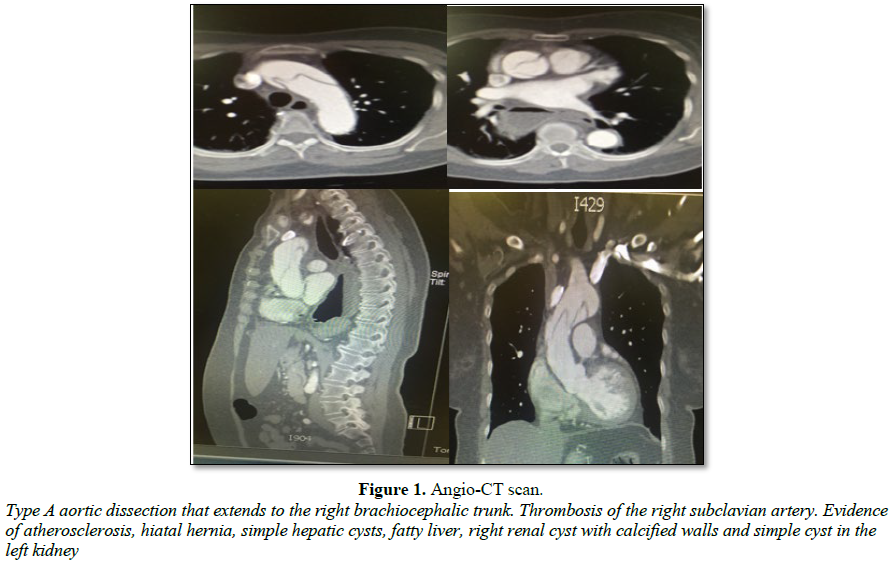

Physical examination revealed hypotension, without altered consciousness or tachycardia, right arm with decreased force, coldness, weak radial pulse and prolonged capillary refill, adequate femoral pulses and normal cardiopulmonary auscultation. Acute aortic pathology was suspected; chest X-rays showed mediastinal widening; due to the high probability and clinical suspicion of an acute aortic syndrome (AAS), an angio-CT scan was requested, showing type A aortic dissection with involvement of the right subclavian artery (thrombosis) and the brachiocephalic trunk. The patient was referred to another institution for assessment by cardiovascular surgery, who analyzed the case and due to the patient’s comorbidities, age and extension of the vascular affection; non-surgical expectant management was decided. She remained in ICU for 24 h. The next day, the patient presented a convulsive episode, followed by cardiorespiratory arrest. No CPR maneuvers were performed due to previous dissent; the patient died (Figure 1).